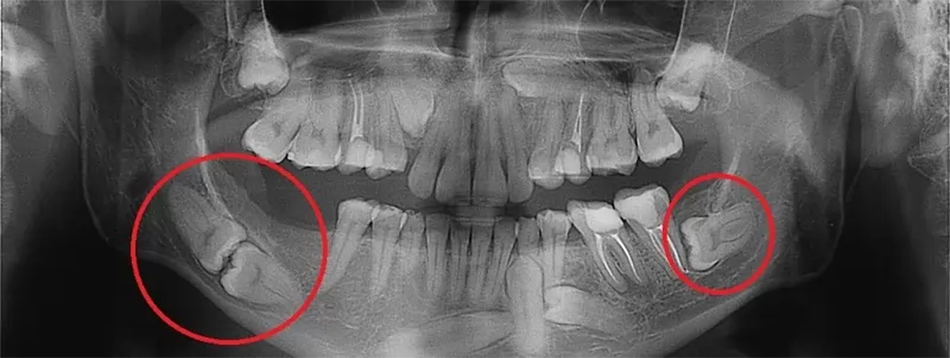

- Ретеновані зуби: Зуби, які не прорізалися повністю, можуть викликати біль, набряк, інфекції або навіть пошкодження кістки.

- Дистоповані зуби: Неправильне положення зубів мудрості може призвести до тиску на сусідні зуби, порушення прикусу або їх руйнування.